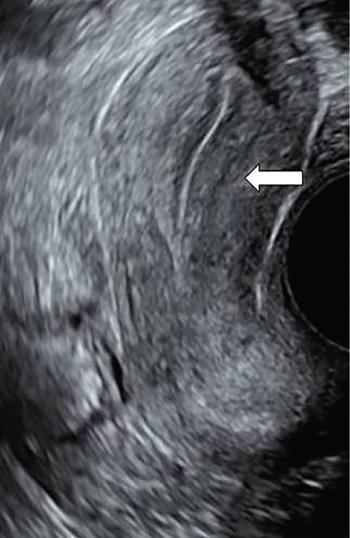

Venkatraman Indiran Bridging vessel sign Multiple vascular channels (white arrows) connecting uterus (black arrow) to an adjacent pelvic mass on imaging studies, is known as the ‘bridging vessel’ or ‘bridging vascular’ sign. Originally described on colour Doppler imaging, but also seen on computed tomography (CT) or magnetic resonance imaging (MRI). Helps in differentiating a mass of uterine origin, typically a subserosal fibroid, from other pelvic masses. Sensitivity and specificity of ‘bridging vessel sign’ in identifying subserosal fibroids range from 90% to 100%. (Best seen when subserosal fibroid is larger than 3 cm in diameter.) Ovarian masses invading the uterus may rarely produce a falsely positive bridging vessel sign. Broccoli sign Submucosal uterine leiomyoma prolapsing into the endocervical canal, along with its stalk in the uterine cavity on sagittal T2-weighted images together is called as ‘broccoli sign’ (white arrow). Submucosal uterine leiomyoma Bunch of grapes Intrauterine mass with cystic spaces without any associated foetal parts on ultrasound (white arrows) classically gives a ‘snow storm’ or ‘bunch of grapes’ appearance. Complete hydatidiform mole Hourglass sign Deep infiltrating endometriosis (DIE) affecting the posterior urinary bladder wall, usually in the midline, causes loss of its distensibility, resulting an hourglass configuration of urinary bladder. Deep infiltrating endometriosis (DIE) Hyperechoic line sign Normal endometrium surrounding the endometrial polyp on ultrasound appear as a hyperechoic rim on transvaginal ultrasound is called as ‘hyperechoic line sign’. Hyperechoic line sign represents a focal intracavitary lesion. Endometrial polyp Indian head dress sign/moose antler sign In deep infiltrating endometriosis (DIE), adhesions between the anterior wall of rectosigmoid and posterior wall of uterus, stretches the muscular layer of the bowel and creates an infiltrative nodule with parallel lines that extend from the adhesion to the rectosigmoid. This is called as ‘Indian head dress sign/moose antler sign’ (white arrow). This is seen on sagittal T2-weighted images as well as transvaginal ultrasound. Deep infiltrating endometriosis (DIE) Interstitial line sign An echogenic line that extends into the upper regions of the uterine horn and borders the margin of the intramural gestational sac is called as the ‘interstitial line sign’ (white arrow). Seen best on transabdominal/transvaginal ultrasound. Specific finding of interstitial pregnancy Mushroom cap sign Mushroom-shaped lesion which is seen displaced into the bowel lumen in patients with solid invasive endometriosis of the rectosigmoid colon on axial or sagittal T2-weighted MRI is called as ‘mushroom cap sign’ (red box and white arrow). Low signal intensity base of the mushroom corresponds to hypertrophy and fibrosis of the muscularis propria, whereas the high intensity cap represents oedematous mucosa and submucosa. Deep infiltrating endometriosis (DIE) Pedicle artery sign Feeding vessel sign Central vessel entering the endometrium from the surrounding myometrium colour Doppler imaging of the endometrium in endometrial polyps is called as pedicle artery sign (white arrow). Endometrial polyps in women with postmenopausal bleeding. (Sensitivity of 76.5%; specificity of 95.3%.) Popcorn ball calcification Dense, amorphous calcifications of uterine fibroids seen on the plain radiographs is called as ‘popcorn calcification’ (white arrow). Confluent, coarse calcification constitutes the most specific radiographic sign of a benign uterine fibroid; but only 10% or fewer of fibroids show calcification. Question mark sign of uterus The uterine corpus that is flexed backward with the fundus of the uterus facing the posterior pelvic compartment and the cervix directed anteriorly toward the urinary bladder, is called as question mark sign of uterus (white arrow). Also called as comma-shaped uterus. 93% specificity and 75% sensitivity in diagnosing adenomyosis uterus. Sliding organs’ sign When the uterus and ovaries glide freely over the posterior and anterior organs (such as rectum and urinary bladder, respectively) during real-time dynamic transvaginal sonography, it is called as ‘positive sliding organs’ sign’. In case of adhesions due to endometriosis, free gliding of organs is absent and is called as negative sliding sign. Snowstorm sign Grainy appearance with low-level homogeneous internal echoes which move slowly downward due to their viscosity seen in endometrioma on transvaginal ultrasound is called as snowstorm sign. Endometriomas Split fibre sign Presence of curvilinear T2 hypointense strands within the degenerated leiomyoma separated by the fluid accumulation and oedema is called as the ‘split fibre’ sign. Split fibre sign on T2-weighted MRI can be used to differentiate hydropic degeneration from other conditions like malignant change. Three-line sign or triple line sign or trilaminar appearance Shortly before ovulation, two additional bright linear echoes outline two hypoechoic layers of endometrium with a central hyperechoic line in the endometrium (white arrow). It is called as the ‘three-line sign’ or ‘triple line sign’ or trilaminar appearance. A triple-line pattern with a moderate endometrial thickness is associated with a good clinical outcome on in-vitro fertilization. Venetian blind shadowing Also known as ‘rain shower’ appearance Heterogeneous myometrial appearance due to hyperechoic heterotopic endometrial tissue and hypoechoic hyperplastic smooth muscle appearing as vertical linear bands of shadows on ultrasound is called as ‘Venetian blind shadowing’. Classically described in uterine adenomyosis; sometimes in uterine fibroids also. Bead on strings sign Thickened endosalpingeal longitudinal folds within a dilated fallopian tube without wall thickening appears as small mural nodules on cross-sectional images on ultrasound is called as ‘bead on strings’ appearance. Seen in chronic salpingitis Beaded tube Multiple constrictions along the course of fallopian tube may form due to scarring is seen in genitourinary tuberculosis and shows a ‘beaded’ appearance. Female genital tuberculosis Cogwheel sign Thickened endosalpingeal longitudinal folds within a dilated fallopian tube with thickened wall appears as small mural nodules on cross-sectional images across the long axis of the fallopian tube on ultrasound (white arrows) produce a characteristic ‘cogwheel’ appearance. Seen in acute salpingitis. The presence of thickened longitudinal folds is pathognomonic for hydrosalpinx. Cobblestone tube Rounded filling defects in cases of fallopian tube tuberculosis are called as the cobblestone pattern. Is an effective radiographic sign of intraluminal scarring and adhesions. Female genital tuberculosis Golf club tube Occlusion of the isthmus or fimbrial end of the fallopian tube and filling up of the tube with serous or clear fluid produces a moderate dilatation at the fimbrial end, produces a ‘golf club–like appearance’. Female genital tuberculosis Halo sign Thin radiolucency seen separating the loculated peritubal collection from the dilated tube, is known as the ‘halo sign’. This radiolucent halo represents the thickened wall of the tube. Female genital tuberculosis Incomplete septation sign Thin linear structures appearing to protrude into the tubular cystic adnexal structures, but not touching the opposite walls is called ‘incomplete septation sign’ of hydrosalpinx. Apparent septae are due to apposition of the inner walls of the dilated and folded fallopian tube. Hydrosalpinx Pipe stem tube Rigid contour of the fallopian tube seen in cases of fallopian tube tuberculosis is called as ‘pipe stem appearance’. Female genital tuberculosis Leash sign Typical eccentric leash of vessels on colour Doppler (white arrow) showing a low resistance placental type of flow on spectral Doppler in fallopian tube ectopic pregnancies is called as leash sign.